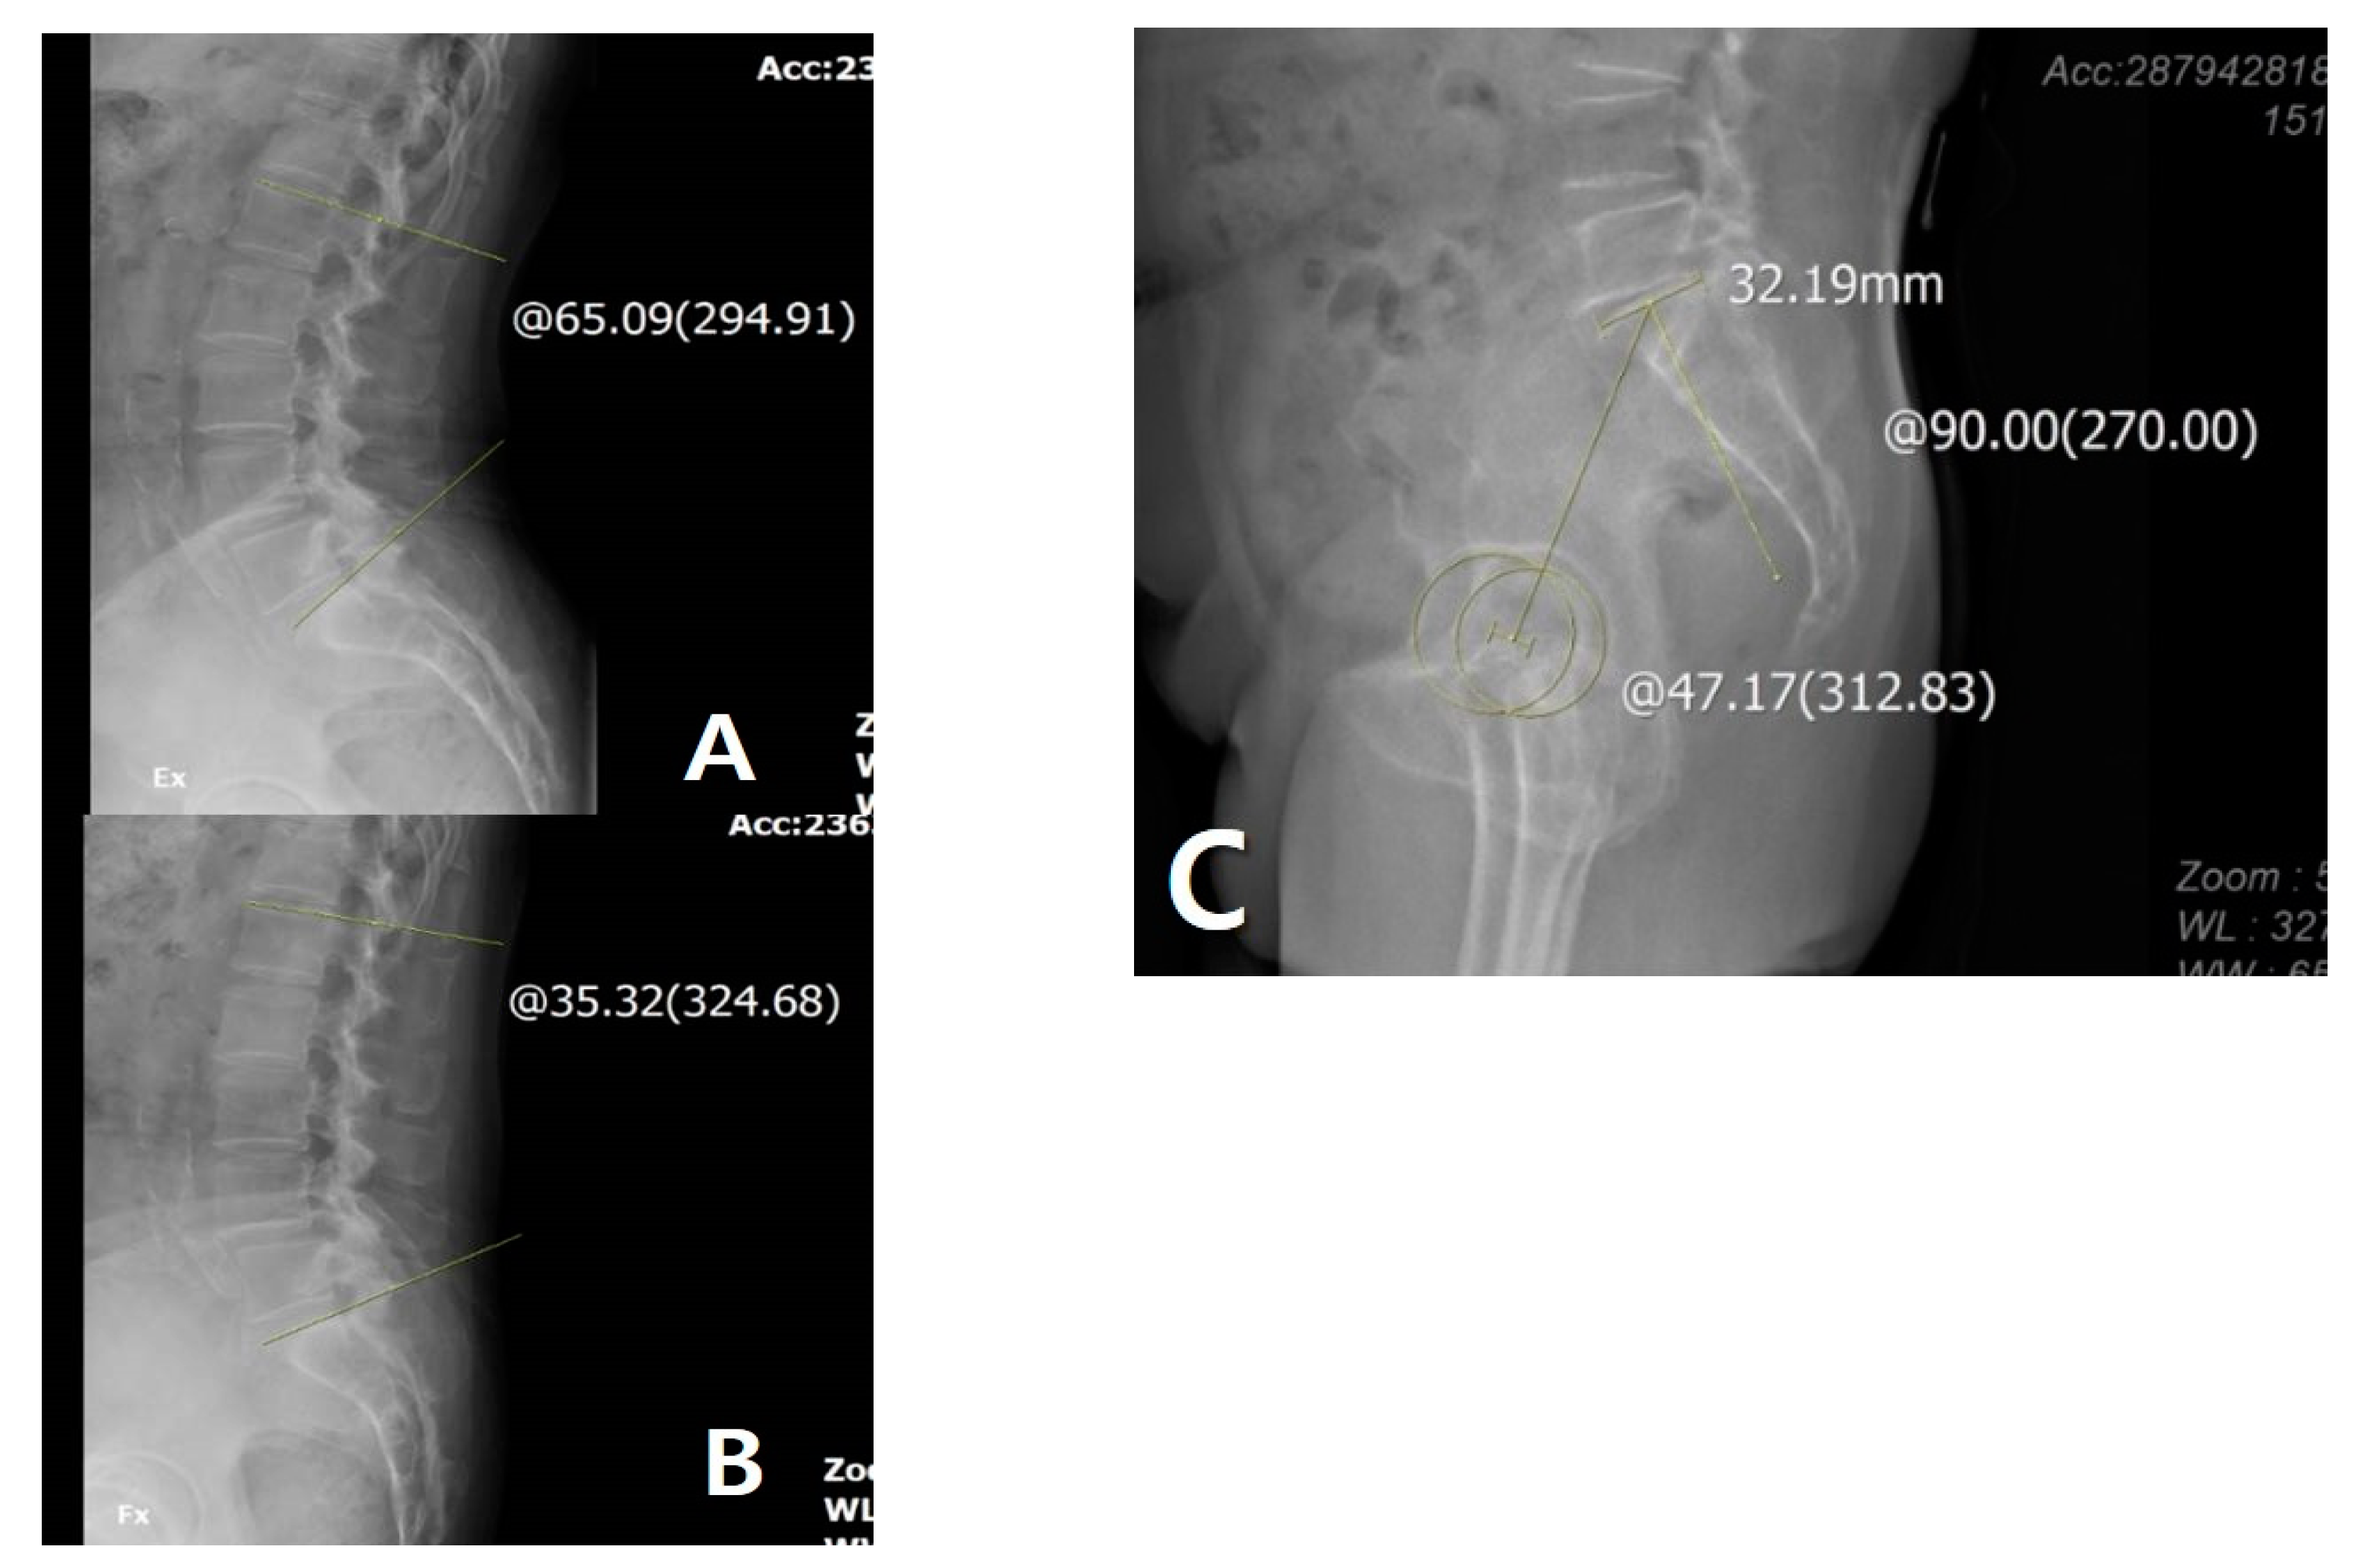

Figure 2. (A) Measurement of lumbar lordosis (LL) on extension view: 65.09°. (B) Measurement of LL on flexion view: 35.32°. (C) Measurement of pelvic incidence: 47.17°. The yellow line and circle are the measurement about lumbar lordosis and pelvic incidence